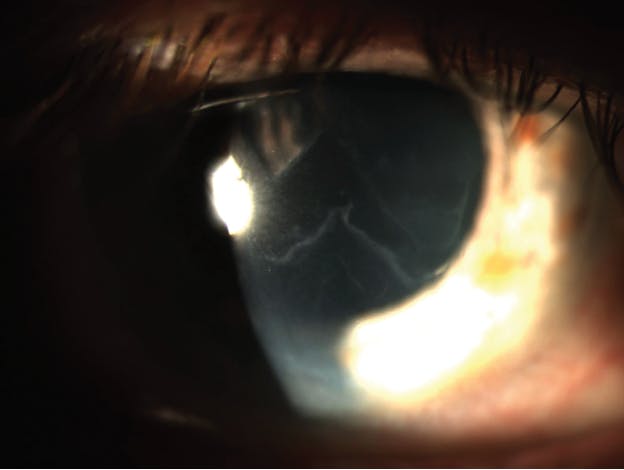

The main symptoms of EBMD are typically ocular irritation, blurred vision, glare, photophobia, and pain. Recurrent corneal erosion (RCE) in EBMD can cause sharp pain, usually in the morning upon waking. RCE usually occurs after a traumatic abrasion in patients with or without EBMD. The pain can range from mild and lasting only a few minutes to severe and lasting hours or days or until treatment is initiated. Surface irregularity and rapid tear breakup time at the area of slightly elevated epithelium overlying the map-like changes, fingerprint lines, and/or microcysts in EBMD may reduce visual acuity. Retroillumination while the pupil is dilated is one of the easiest ways to view EBMD (Figure 1).3